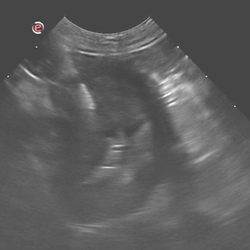

Ultrasound guided procedure

FNA, Tru-cut biopsy, abdominocentesis, pleurocentesis, pericardiocentesis, cholecystocentesis.